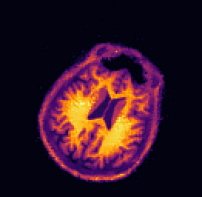

IV-B PET-MR reconstruction

In this experiment we consider PET-MR, where we aim to reconstruct a tracer distribution using a fully sampled T1-weighted MR image of size 144×144144144144\times 144 as side information. The forward operator is modelled by a parallel beam X-ray transform with 200 angles equispaced in (0,π]0𝜋(0,\pi] and 192 bins. The sinogram data were simulated using a ground truth image deformed with respect to the side information through the rigid deformation

ϕrigid(x)=Rθx+b,subscriptitalic-ϕrigid𝑥subscript𝑅𝜃𝑥𝑏\displaystyle\phi_{\texttt{rigid}}(x)=R_{\theta}x+b, (23)

where Rθsubscript𝑅𝜃R_{\theta} is a rotation matrix (12) with angle θ=0.15.7𝜃0.1superscript5.7\theta=0.1\approx 5.7^{\circ} and b=(0.02,0.08)T𝑏superscript0.020.08𝑇b=(0.02,0.08)^{T} is a translation vector.

In this experiment we simulate data based on a dTVdTV\operatorname{dTV}-regularized reconstruction of clinical data, see [28]. The data is an instance of a Poisson random variable with parameter Ax+r𝐴𝑥𝑟Ax+r, where the background r𝑟r is chosen as constant 7 and the forward operator is scaled to about 1.31061.3superscript1061.3\cdot 10^{6} expected counts in the data. Correspondingly, the data fidelity used is the Kullback–Leibler distance (4).

Again, images are in [1,1]2superscript112[-1,1]^{2} and hence the pixel width of the side information is 0.0138¯0.013¯80.013\overline{8}. The resolutions and regularization parameters in Algorithm 2 were chosen as nk=(92,182,362,722,1442)subscript𝑛𝑘superscript92superscript182superscript362superscript722superscript1442n_{k}=(9^{2},18^{2},36^{2},72^{2},144^{2}) and αk=4101(104,103,102,10,1)subscript𝛼𝑘4superscript101superscript104superscript103superscript102101\alpha_{k}=4\cdot 10^{-1}\cdot(10^{4},10^{3},10^{2},10,1). For the TVTV\operatorname{TV} experiment we used αk=4102(104,103,102,10,1)subscript𝛼𝑘4superscript102superscript104superscript103superscript102101\alpha_{k}=4\cdot 10^{-2}\cdot(10^{4},10^{3},10^{2},10,1).

The sinogram data and the deformed image which was used to generate the data are shown in the top row of Figure 5. Furthermore, we show the side information and the ground truth image. In the second row of Figure 5 we show four different reconstructions: the first one obtained through filtered back-projection, the second one utilizing TVTV\operatorname{TV} regularization, the third one using the three-step method (22), and the fourth one being the proposed method. The first two methods, which do not use the side information or correct any motion, exhibit poor image quality due to strong noise in the sinogram. On the other hand, both the three-step and the proposed method correct the deformation and the reconstructions are in very good agreement with the ground truth image.

Quantitatively, the SSIM values for filtered back-projection and TVTV\operatorname{TV} are relatively low whereas they are comparably high for both the three-step and the proposed method, with slightly better values for the proposed method. The same is also true for the relative errors of the computed deformation fields.